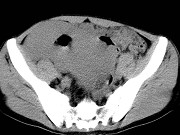

- 单项选择题男,23岁, 下腹部肿块伴持续性钝痛1月余,影像所见如图, 最可能的诊断为 ( )

A、小肠癌

B、小肠淋巴瘤

C、小肠转移瘤

D、小肠结核

E、小肠间质瘤